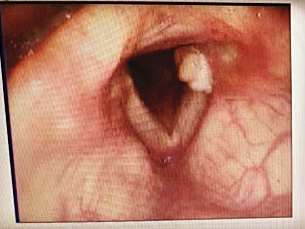

手术后再次复发的声带肉芽肿

两年前,包大哥咳嗽不止,后来痰里还经常有血,包大哥赶紧去医院检查,检查结果是声带后端长了肉芽肿,要手术才能切掉。害怕发展成肿瘤的包大哥马上做了全麻支撑喉镜肉芽肿切除手术。包大哥回忆说,当时医生只切了一个大的肉芽肿,后来一个月后复查才发现,声带上长了一大一小两个声带肉芽肿,大的手术切了可又长出来了,原来没发现的那个小的也长大了,包大哥紧接着又做了第二次手术,没想到的是,这个声带肉芽肿没完没了,像是缠上了包大哥,第二次手术完一个月,肉芽肿又冒出来了。